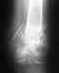

Re: Компрессионный перелом 11 грудного позвонка

С вашим переломом можно ходить в корсете, а сейчас уже надо делать контрольные снимки